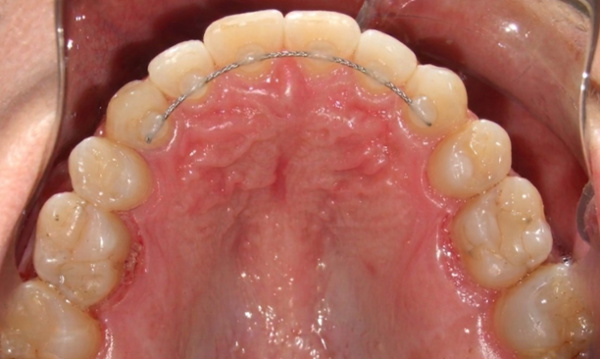

Orthodontic treatment for adults often involves managing complex dental histories. This patient in his 40s presented with a collapsed, square-shaped maxillary arch, a crossbite, and shifted midlines. Complicating the case were congenitally missing lower second premolars and over-retained primary first molars. Under the specialized care of Dr. Jesus Martinez, we utilized Rapid Palatal Expansion (RPE) to restore proper arch width and traditional braces to correct the alignment and bite. Strategic management of the primary teeth and missing permanent teeth allowed us to achieve a stable, functional result secured with fixed retainers. We invite you to schedule a personal evaluation at our concierge Miami or Kendall offices, where the specialist evaluates every case personally from start to finish.